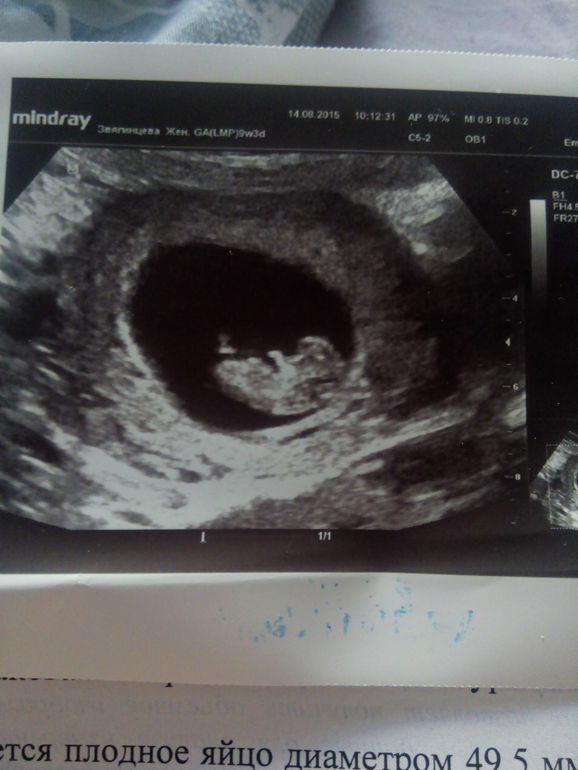

Беременность- 1 триместр ( только до 10 недель)Мы ещё подросли))) Плодное яйцо 49,5 мм; Эмбрион КТР 28,2 мм; ЧСС 174; ЖМ 3,2 мм. Лежала В больнице с тонусом по передней стенке, выписали 7 августа без всяких тонусов, сегодня на узи...тонус по задней стенке...через неделю????? Ну что ж такое???

Солнышко моё))) Нам 9 недель 4 дня))